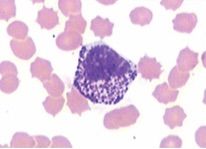

1. neutrofielen

Annotations:

• eerste verdediging tegen infecties

1. primaire granules

• of azurofiele granules              groter en peroxidase positief

1. secundaire granules

• specifieke granules keiner een geen peroxidaseactiviteit